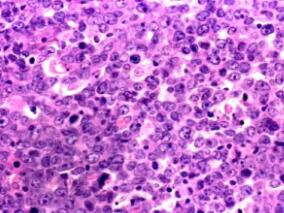

1小时条评论2016年11月,发表在《Leuk Lymphoma》的一项在日本开展的研究考察了米托蒽醌、依托泊甙和阿糖胞苷低剂量联合(迷你MEC)治疗复发或难治急性白血病的安全性和有效性。 米托蒽醌(MIT)、依托泊苷(ETP)和阿糖胞苷(Ara-C)(MEC)是急性白血病常用的挽救化疗方案,...